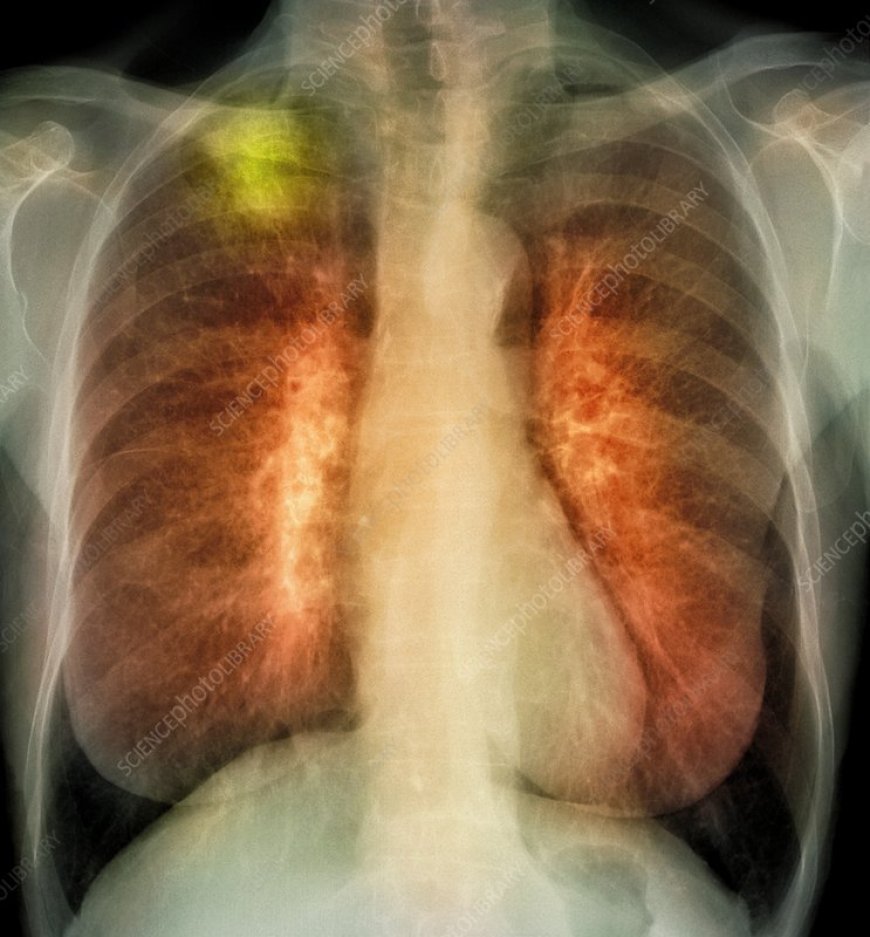

नॉन-स्मोकर्स में भी बढ़ रहा लंग कैंसर का खतरा, डॉक्टरों ने बताए 5 शुरुआती संकेत

लंग कैंसर के शुरुआती लक्षण इतने सामान्य होते हैं कि लोग उन्हें नजरअंदाज कर देते हैं, जैसे लगातार खांसी रहना, सांस फूलना, या हमेशा थकान महसूस करना। लेकिन डॉक्टर कहते हैं कि अगर कैंसर की शुरुआत में ही पहचान कर ली जाए, तो इलाज के नतीजे बहुत अच्छे मिलते हैं। तो आइए डॉक्टर से जानते हैं इसके शुरुआती लक्षण।

इस मामले में मैक्स सुपर स्पेशियलिटी हॉस्पिटल की डाक्टर अनादी पचौरी का कहना है कि अक्सर लोग सोचते हैं कि खांसी या गले की खराश मौसम की वजह से है, लेकिन अगर खांसी तीन हफ्तों से ज्यादा बनी रहे, सांस लेने में तकलीफ हो, आवाज भारी हो जाए, या थकान हमेशा बनी रहे, तो इसे हल्के में न लें। कभी-कभी बलगम में खून के निशान भी दिख सकते हैं। ये लक्षण तुरंत जांच करवाने का इशारा देते हैं। एंड्रोमेडा कैंसर हॉस्पिटल के डॉ. अरुण कुमार गोयल कहते हैं कि लगातार खांसी, वजन घटना, सीने या पीठ में दर्द, बार-बार सीने में इंफेक्शन जैसे लक्षण भी फेफड़ों के कैंसर के शुरुआती संकेत हो सकते हैं। स्मोकर्स या जो प्रदूषित जगहों पर रहते हैं, उन्हें खास सतर्क रहना चाहिए।